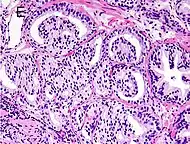

Gleason score 9 (4+5) with cribriform glands, some with necrosis

Gleason score 10 (5+5) with cords of cells

Gleason 5

Neoplasms have no glandular differentiation (thus not resembling normal prostate tissue at all). It is composed of sheets (groups of cells almost planar in appearance (like the top of a box), solid cords (group of cells in a rope like fashion running through other tissue/cell patterns seen), or individual cells. You should not see round glands with lumenal spaces that can be seen in the other types that resemble more the normal prostate gland appearance.[4][7]